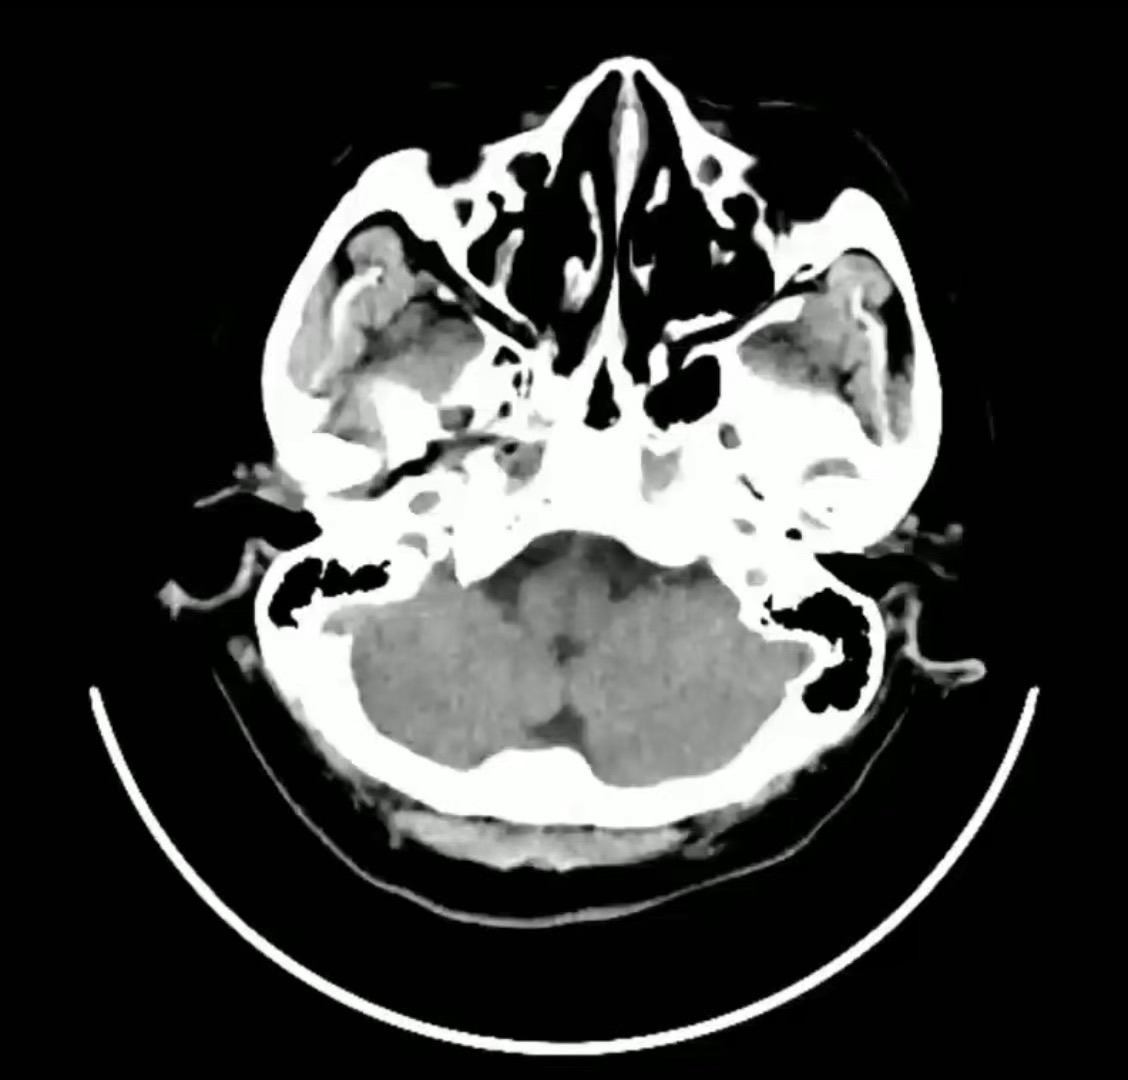

病例【神经】CT与MR孰弱孰强?有时候,确需联合应用!发作性右侧肢体活动不灵1天,女58岁

【主诉】:发作性右侧肢体活动不灵1天。

【检查】:CT,不仔细看,极易漏诊。

MR 急性出血还是梗塞?

出血性脑梗死 (18)